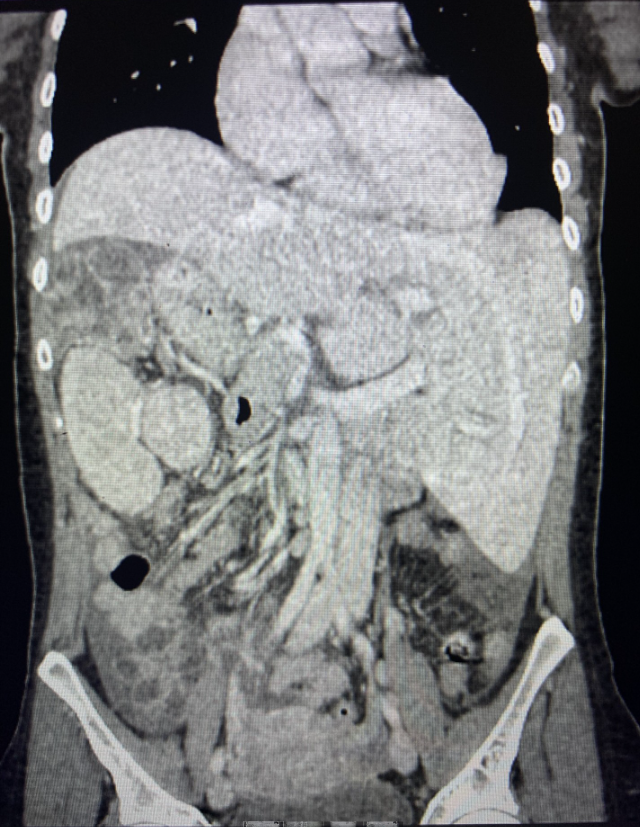

TAC Abdominal: Situs inverso de órganos intraabdominales. Imagen hipodensa de aspecto pseudocoleccionado subdiafragmático derecho de 89 x 63 mm, asociado a aumento de densidad y trabeculación de la grasa adyacente, que no consigue caracterizar por completo. Leve engrosamiento parietal hipodenso segmentario del colon izquierdo, asociado a aumento de densidad y trabeculación de la grasa adyacente, altamente sugestivo de colitis, de etiología indeterminada. Presencia de líquido libre en ambas gotieras y en pelvis.

Juicio clínico: Situs inverso de órganos intraabdominales y masa subdiafragmática.

Paciente intervenida por infarto de bazo superior y hemoperitoneo de 450 cc.